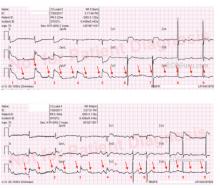

This ECG was recorded from a 75-year-old man with substernal chest pain and diaphoresis. It shows a pretty classic picture of acute inferior wall M.I. The second ECG is a repeat tracing with the V4 wire moved to the V4 Right position, and it is positive for right ventricular M.I. The patient was found to have a 100% occlusion of the right coronary artery, which was opened and stented in the cath lab.

There are several other examples of IWMI with RVMI in our archives, so we will confine this commentary to the ECG signs that make these tracings so typical of right coronary artery occlusion. Once you are familiar with the typical pattern of IWMI / RVMI, it is easy to see, even when the ST elevation is subtle (as this one certainly is NOT).

Signs of IWMI in these ECGs are:

· ST elevation in inferior leads II, III and aVF.

· Reciprocal ST depression in leads I and aVL.

Signs of RVMI in these ECGs are:

· ST elevation in V4 right.

· ST elevation in V1 without ST elevation in V2.

· ST elevation in lead III is greater than ST elevation in lead II.

Other common findings in right coronary occlusion that are seen in these ECGs:

· ST depression in V2. If not for the RVMI causing elevation in V1, there would be ST depression in V1 also. This is a reciprocal ST depression, reflecting STE in the posterior wall. The posterior wall is called the lateral wall by some because it is oriented behind the anterior wall, but toward the patient’s left side. This area across from V1, V2, and sometimes V3 can have ST elevation if an inferior wall M.I. is large enough to extend up toward the base of the heart. Electrodes placed on the left side of the back might show the STE.

· Bradycardia and heart block. Sinus and AV node blocks often occur in IWMI because the two nodes usually have the same blood supply as the inferior wall and right ventricle. AV blocks are usually of the “Type I” variety. There may be varying amounts of first-degree AVB, second-degree AVB, Type I (Wenckebach), and even third-degree, or complete heart block. In the first ECG, at 3:17, we see some 2:1 AVB. There are also some periods where there is AV dissociation with junctional escape, or possibly very long PR intervals (beats 1,5,6). In the second ECG, at 3:27, we see a slight increase in the sinus rate with Wenckebach periods (beats 5-8).

Of note, ECG #2 (Bottom) was obtained 10 minutes after ECG #1 (Top). ECG #2 is easier to look at first. This begins with 2:1 AV conduction (Mobitz I) for the first 4 beats in ECG #2. Note that the PR intervals preceding beats #1,2,3,4 appear to be normal and constant. There are then two 3:2 Wenckebach cycles at the end of the tracing (beats #5,6; and 7,8 in ECG #2) — and this confirms our diagnosis!

Things were a bit more complex 10 minutes earlier in ECG #1 (Top). I believe there probably are two 2:1 cycles (beats #4 and 5) — since the PR intervals preceding beats #4 and #5 are similar to the PR intervals preceding what we KNOW are 2:1 cycles in ECG #2. But for beats #2 and 3 in ECG #1 — there is variation in the PR interval preceding these QRS complexes. So one wonders if there is higher-grade AV block at this point? Once again, knowing the clinical context is invaluable — since it is NOT uncommon to go back-and-forth between Mobitz I 2nd-degree AV block and complete AV block with narriow QRS escape during the early hours of acute inferior STEMI. This may be what we see here. Toward the end of ECG #1 — the R-R interval becomes more regular — so this probably reflects junctional escape. But because the R-R interval between beats #2-3 is LESS than the R-R interval between beats #6-7; 7-8; and 8-9 toward the end of the tracing — it is unlikely that complete AV block was present, but rather some “higher-grade” 2nd-degree. And as we see in ECG #2 — 10 minutes later, a much clearer pattern of Mobitz I with 2:1 and 3:2 AV conduction emerges.

As to the 12-lead ECGs — I’ll add to Dawn’s comments by suggesting that although ECG #2 with right-sided lead V4 confirmed the diagnosis of acute RV infarction — this additional tracing was NOT needed for diagnosis given what we already see in ECG #1. There is obvious acute inferior STEMI in ECG #1. The presence of more marked ST elevation in lead III > II suggests acute occlusion of the RCA ( = Right Coronary Artery). What is unusual about ECG #1 is the very marked ST coving and elevation in lead V1! There is ST depression in lead V2, but only minimal. Putting the clinical situation together — the relatively limited amount of ST depression we see in lead V2 reflects associated posterior involvement. In this setting, isolated ST elevation in lead V1 almost certainly indicates acute RV (right ventricular) involvement, perhaps already with some RV dilatation. That’s because lead V1 is a “right-sided” lead — and whenever you see a flat or slightly elevated ST segment in lead V1 in a patient with acute inferior ST and obvious ST depression in V2, V3 — you can suspect RV involvement. Those are the patients for whom right-sided leads DO benefit — because you can then confirm acute RV involvement with ST elevation in V2R, V3R, V4R. But when you see dramatic isolated ST elevation in lead V1 (as we do in ECG #1 here) — you already KNOW you are dealing with acute occlusion of a proximal RCA lesion. Especially in view of the associated rhythm disturbance — urgent cath/PCI is essential for optimal outcome.